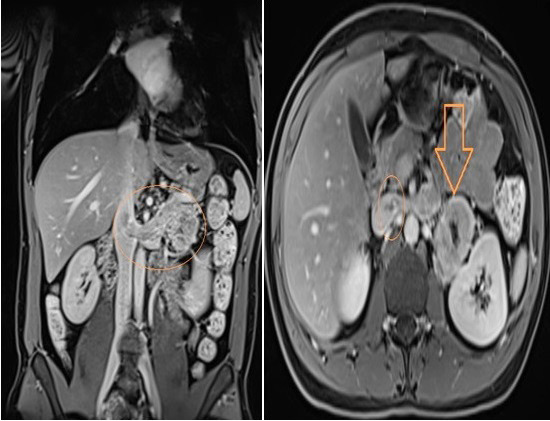

Pheochromocytomas are potentially malignant and may manifest with vascular thrombi. We present the treatment of a patient with pheochromocytoma and tumor thrombosis of the renal vein and inferior vena cava. A thirty-eight-year-old male patient was admitted complaining of abdominal pain and headache. High levels of urinary catecholamine were detected. Magnetic resonance imaging revealed left pheochromocytoma with thrombosis of the inferior vena cava and the left renal vein. A left adrenalectomy and a thrombectomy with cavotomy were performed. The pathology results reported a 9.5 cm malignant pheochromocytoma. The patient's symptoms dissipated after the operation and there were no signs of recurrence at the two-month follow-up. Preoperative radiological diagnostic examinations are valuable in the planning of pheochromocytoma surgery. We believe that adrenalectomy and thrombectomy can be performed on pheochromocytoma patients with vascular thrombi with low morbidity.